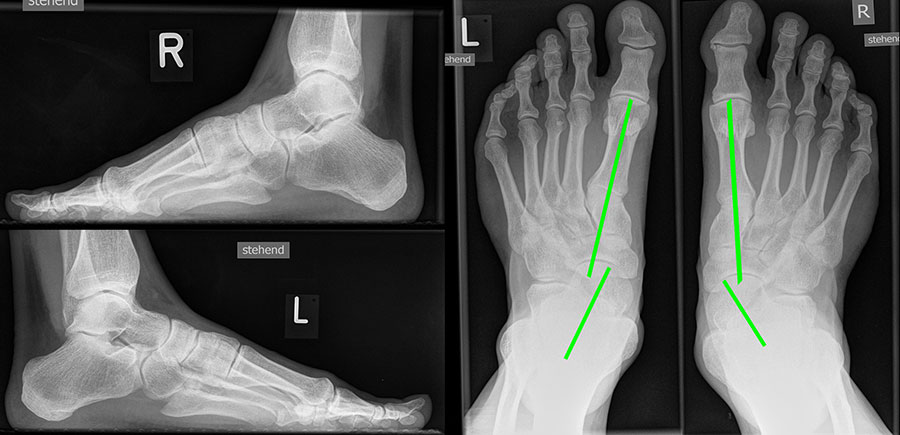

Bei Insuffizienz der tibionavicularen Bandanteile oder des Spring-Ligaments zeigen die konventionellen Aufnahmen eine Konstellation wie bei einer Tibialis posterior Insuffizienz mit Vorfußabduktion, eingesunkenem Längsgewölbe und vermehrtem Rückfußvalgus (Abbildung 3).

Vermehrter Rückfußvalgus links bei chronischer Instabilität des Deltabandes. Die wichtigste Differenzialdiagnose ist die Insuffizienz der Tibialis posterior Sehne.